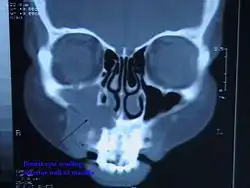

CT scan through head showing a right periapical cyst